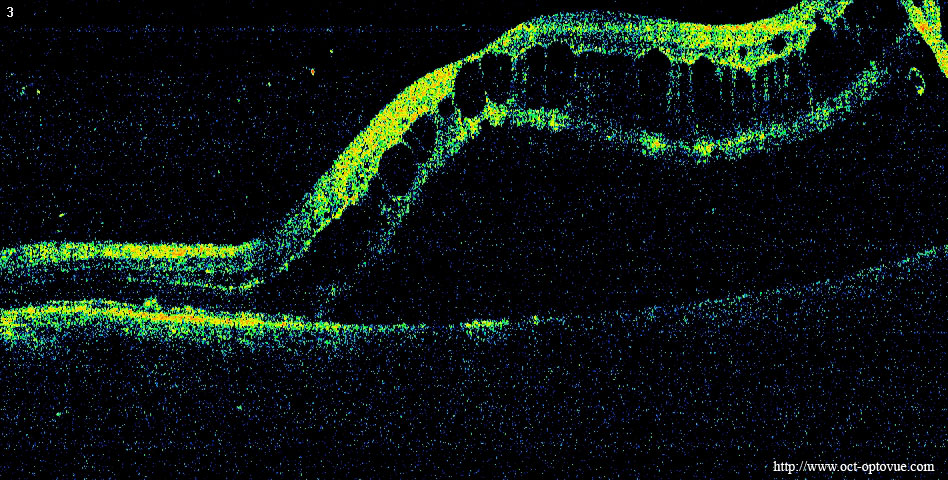

www.docteur-leroy.comDécollement Rétine

www.docteur-leroy.comDécollement Rétine

www.retinesud.frDécollement Rétine

www.retinesud.frDécollement Rétine

www.oct-optovue.comLe Décollement De Rétine • Vision Dix

www.oct-optovue.comLe Décollement De Rétine • Vision Dix